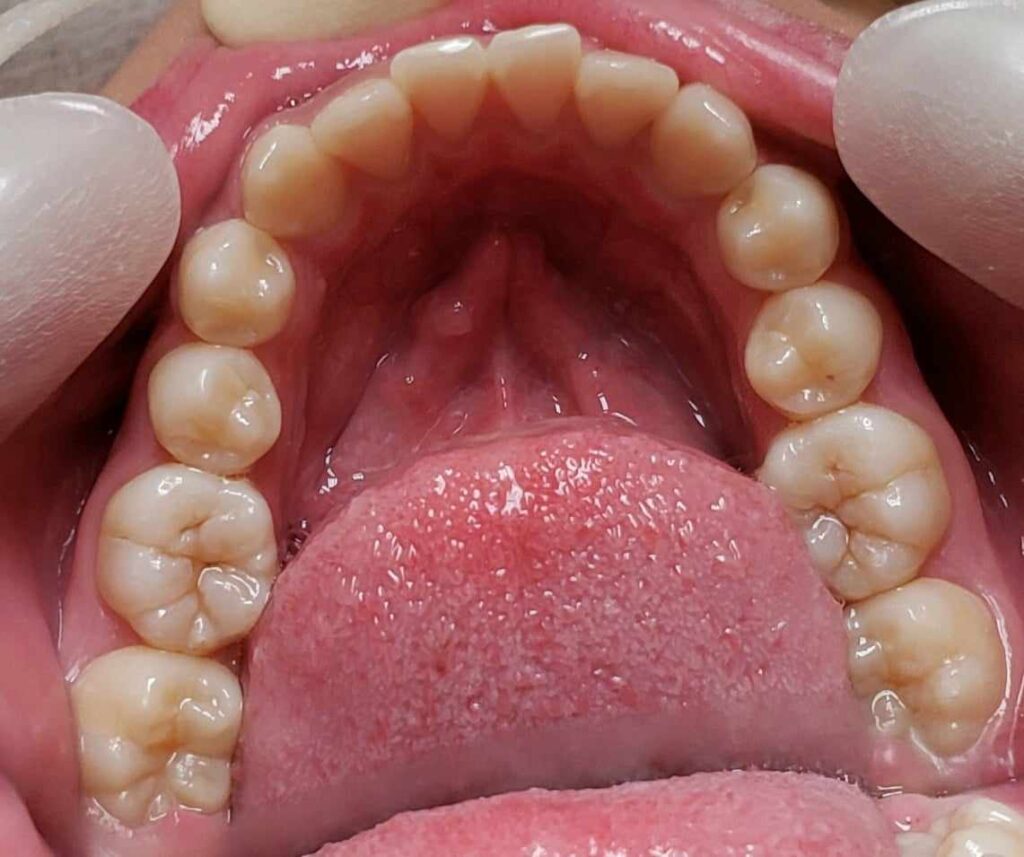

治療前

• 初診:2012年、9歳女児、

• 主訴:出っ歯と歯のがたがたが気になる。

• 診断:1級過蓋咬合、上下前歯叢生、上顎左右側切歯クロスバイト

• 治療方針:非抜歯で行う。虫歯予防(フッ素)、歯磨き指導、上下拡大床→最小限のデイスキング→マウスピース矯正→下親知らずの抜歯、保定→メンテナンス